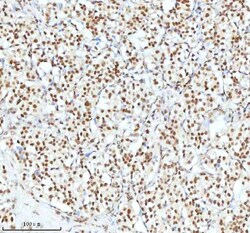

Reconstitute with 0.2 mL of distilled water to yield a concentration of 500 μg/mL. Positive Control - WB: human LNCAP whole cell, human Hela whole cell, human 293T whole cell, human HepG2 whole cell, human Jurkat whole cell, human K562 whole cell, human A549 whole cell, human A431 whole cell. IHC: human bladder cancer tissue, human bladder cancer tissue, human colon adenocarcinoma tissue, human colon adenocarcinoma tissue, human glioblastoma tissue, human glioblastoma tissue, human liver cancer tissue, human liver cancer tissue, human lung adenocarcinoma tissue, human lung adenocarcinoma tissue, human pancreas ductal adenocarcinoma tissue, human pancreas ductal adenocarcinoma tissue, human testicular seminoma tissue, human testicular seminoma tissue. ICC/IF: U2OS cell. Flow: A431 cell. Store at -20°C for one year from date of receipt. After reconstitution, at 4°C for one month. It can also be aliquotted and stored frozen at -20°C for six months. Avoid repeated freeze-thaw cycles.